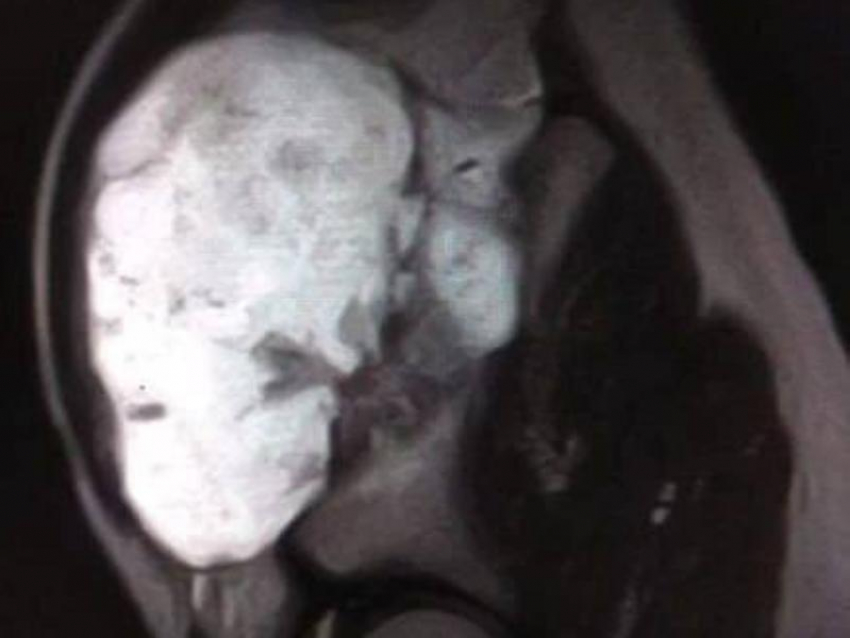

В Воронеже врачи областной детской клинической больницы №2 провели сложную операцию 13-летнему мальчику с крупным костным образованием.

Юный пациент обратился к медикам с жалобами на дискомфорт и ограничение подвижности. При обследовании специалисты обнаружили внушительный нарост на кости размером 12×9×7 сантиметров. По словам врачей, образование не только мешало нормально двигаться, но и представляло серьёзную угрозу – при дальнейшем росте оно могло повредить тазобедренный сустав и привести к осложнениям.

Медики приняли решение о проведении операции. Хирургическое вмешательство оказалось непростым из-за размеров образования и его расположения, однако врачам удалось аккуратно удалить нарост и избежать повреждения важных структур.